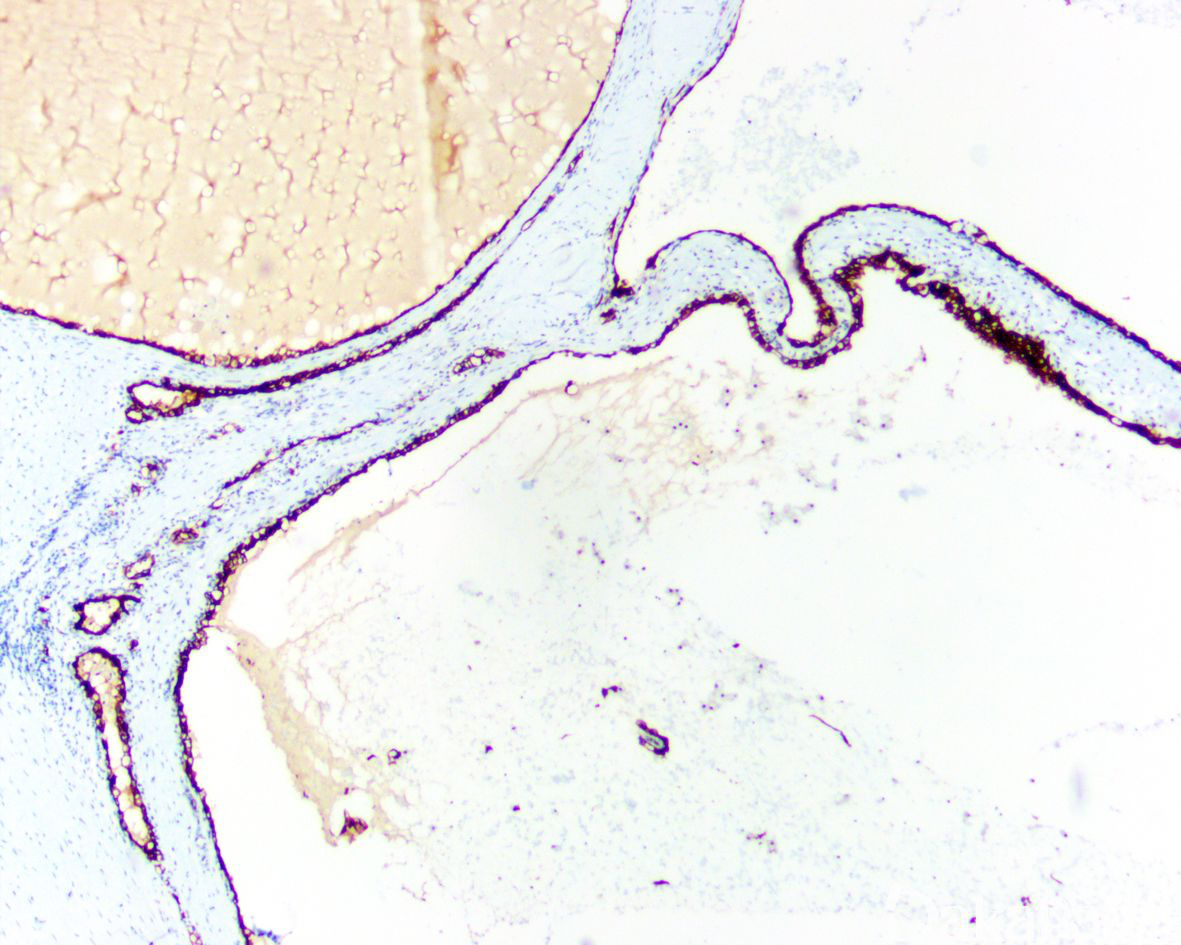

完全由囊腔构成的肿瘤,囊腔间隔内有小灶状透明细胞,形态上与低级别透明细胞肾细胞癌不能区别,无复发及转移报道。

平均直径 4-7cm,大体检查肿瘤有包膜,完全由大小不等的囊腔组成,囊内充以浆液性或血性液体,囊间隔窄偶见钙化,肉眼可见的实性囊壁结节应排除该肿瘤的诊断;

多数囊腔内衬覆单层上皮,细胞胞质透明或淡染,细胞核小而圆,染色质深染而致密,无核仁或小核仁(1-2 级);

囊腔间隔由纤维组织构成,常有致密的胶原,部分间隔内可见灶状透明细胞,这些细胞与囊腔的内衬上皮相似,呈小灶状或簇状聚集,不形成大的结节,似组织细胞或淋巴细胞,周围有收缩的人工假象; 6.20%以上病例间隔内有钙化,偶见骨化生;